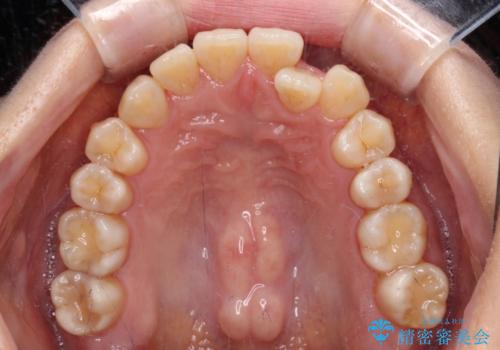

クロスバイトの前歯を改善 ワイヤー装置で楽々矯正治療

- 前歯のクロスバイトを改善したいとのことで来院された患者様です。

マウスピース矯正は自己管理が煩わしいとのことで、ワイヤー装置による矯正治療を行うこととしました。

舌の突出癖が認められたため、デコボコ改善に伴い前歯が前突する可能性があったため、舌のトレーニングをしっかりと行うよう指導しながら治療を進めることとしました。

左下の奥歯は根管治療後に放置されていたため、咬み合わせを調整しながら矯正治療を行い、最後にオールセラミッククラウンにて補綴治療を行うこととしました。